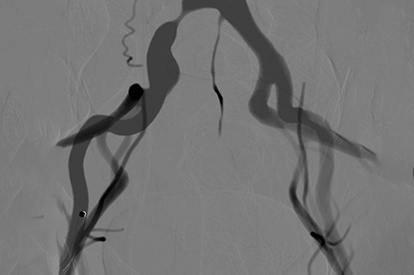

EVAR (Endovascular Aneurysm Repair) Module

Iliac Intervention Module

Endovascular Trauma Management Module